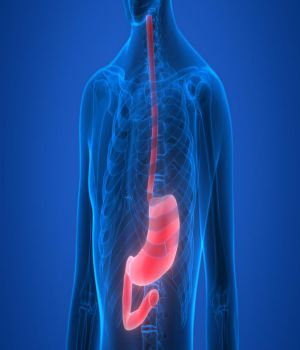

Our digital X-Ray services at home are performed by highly trained professionals using an advanced portable DR System machine that allows for the most accurate X-Ray depictions available on the market today for almost all parts of the human body.

X-ray Barium Meal Upper G.I.T. | Pricing in Delhi at Ganesh Diagnostic